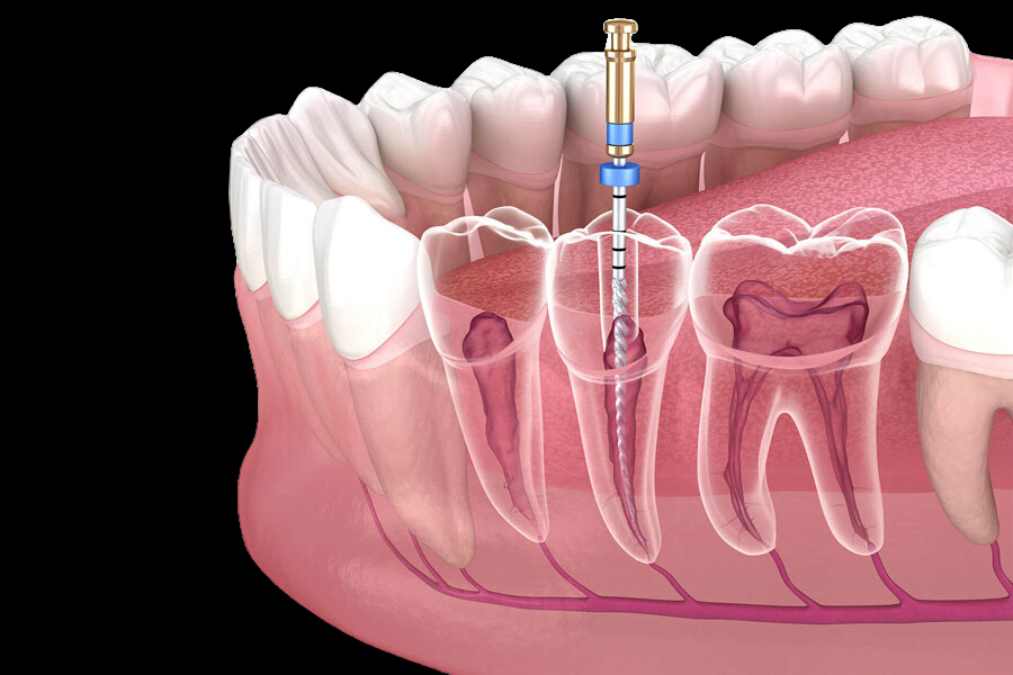

Elevación del seno maxilar

La elevación del seno maxilar es un procedimiento quirúrgico necesario cuando el hueso del maxilar superior no tiene suficiente altura para colocar implantes dentales. Este problema ocurre principalmente en la región posterior del maxilar, donde se encuentran los senos maxilares, cavidades naturales que pueden ocupar el espacio óseo requerido para el implante.

Durante esta cirugía, se eleva la membrana del seno maxilar y se inserta un injerto óseo para aumentar la altura del hueso. Esto facilita la colocación del implante. Es un procedimiento clave para pacientes con pérdida ósea en esta zona.